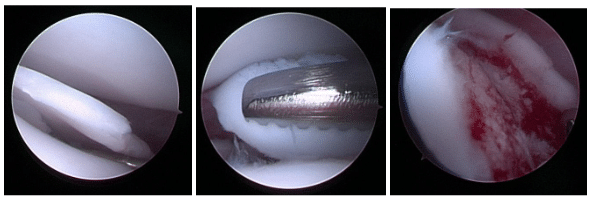

This thickened cartilage begins to detach from the underlying bone, just as can be seen in the picture, and this is painful. The only difference between osteochondrosis and osteochonditis dissecans (OCD), is that OCD is when that flap of cartilage actually becomes or starts lifting up away from the underlying bone, but the underlying process is the same.

On the right is an image of an open arthrotomy for a dog shoulder OC/OCD, with the right image showing the defect after debridement. The image is grainy and pixelated because open arthrotomy is rarely done these days, with modern orthopedic veterinary surgeons preferring minimally invasive arthroscopy.

Arthroscopic Debridement

Arthroscopic debridement is the same in principle as open debridement. The flap of cartilage is removed, the remaining bone bed is scraped to clean it and facilitate bleeding, and the defect fills in (to some degree) with healing fibrocartilage. The difference between this and open debridement is that arthroscopic treatment means this is performed entirely with an arthroscope through two or three small incisions (each about 5-8 millimeters long).